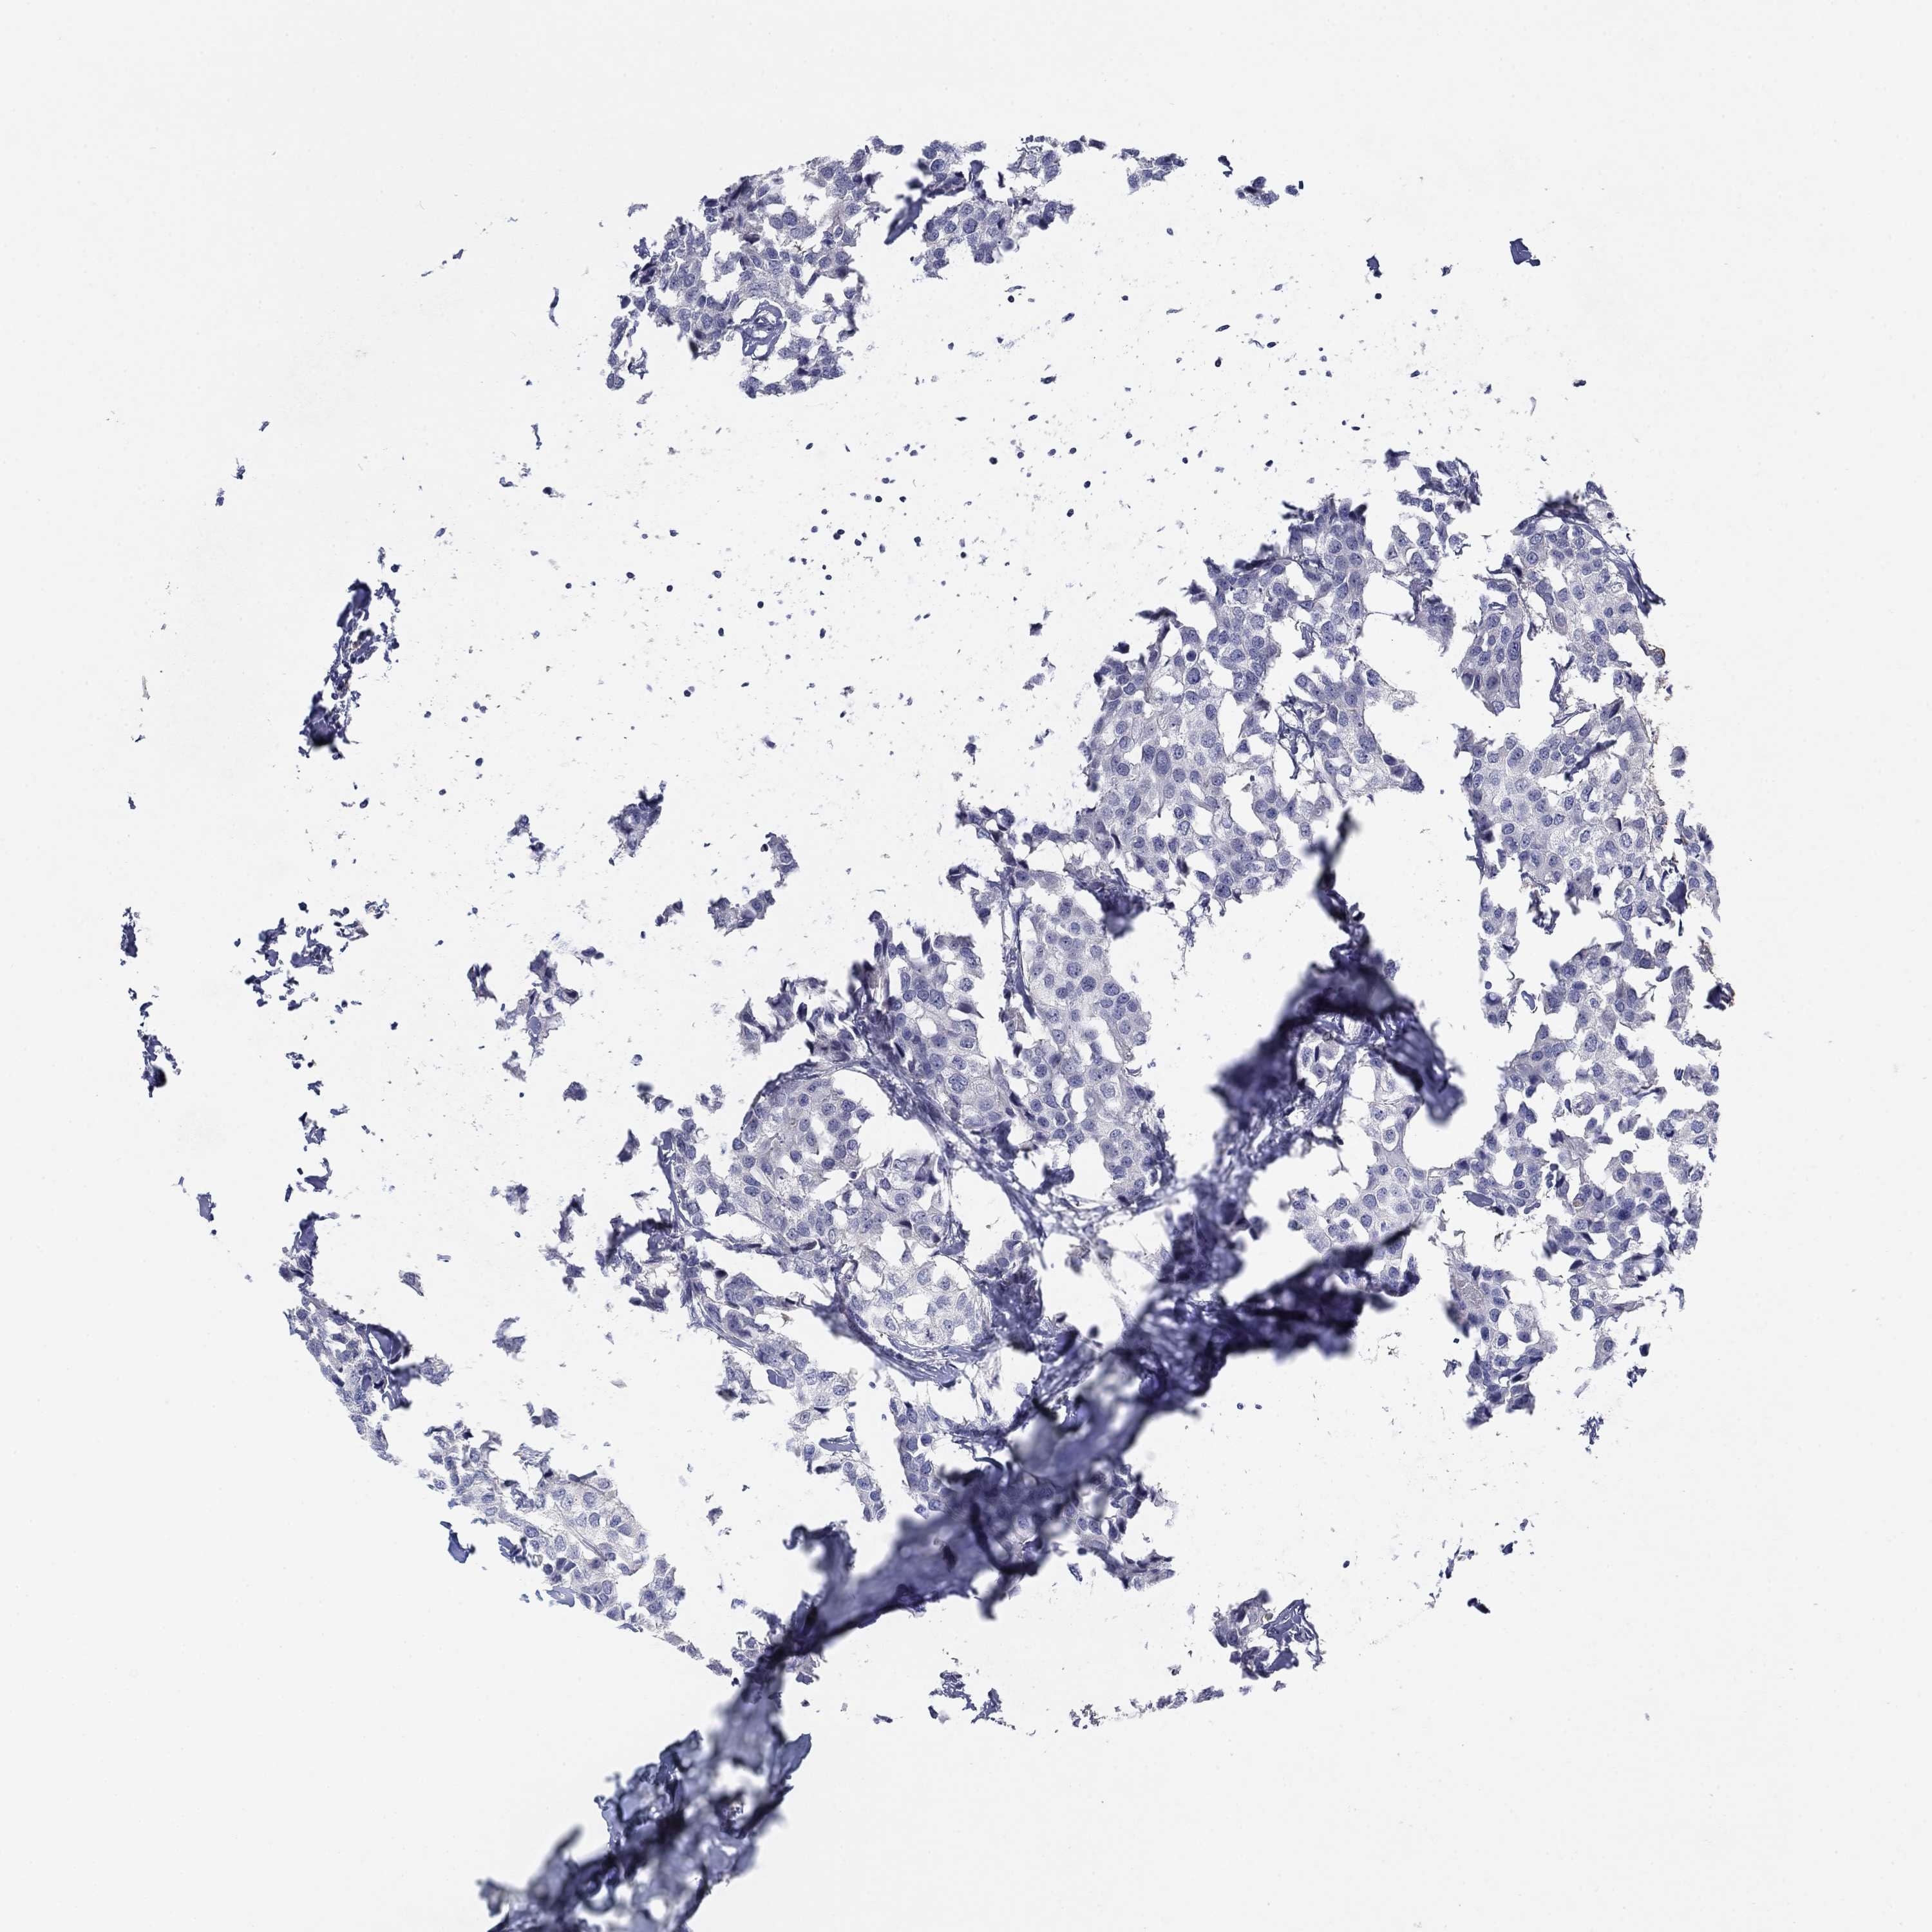

Breast cancer

Human cancer